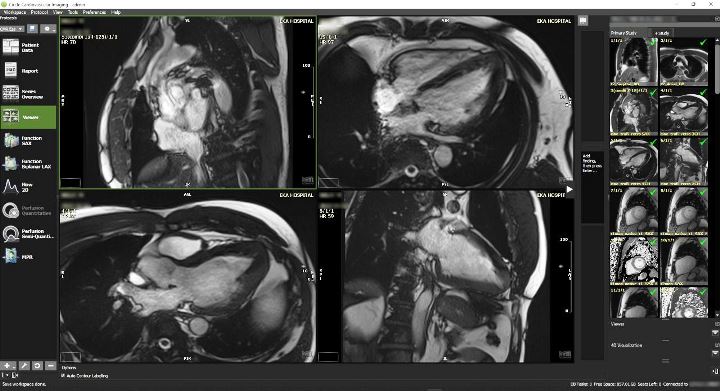

1. Magnetic Resonance Imaging (MRI) Cardiac Scan

MRI scan adalah tindakan cardiac imaging yang menggunakan teknologi magnet dan gelombang radio dalam menganalisis serta memberikan gambaran struktur jantung. Melakukan MRI jantung dapat mengantisipasi adanya kejadian sudden death atau kematian mendadak pada pasien gagal jantung, serta pasien-pasien yang memerlukan pemasangan ICD.